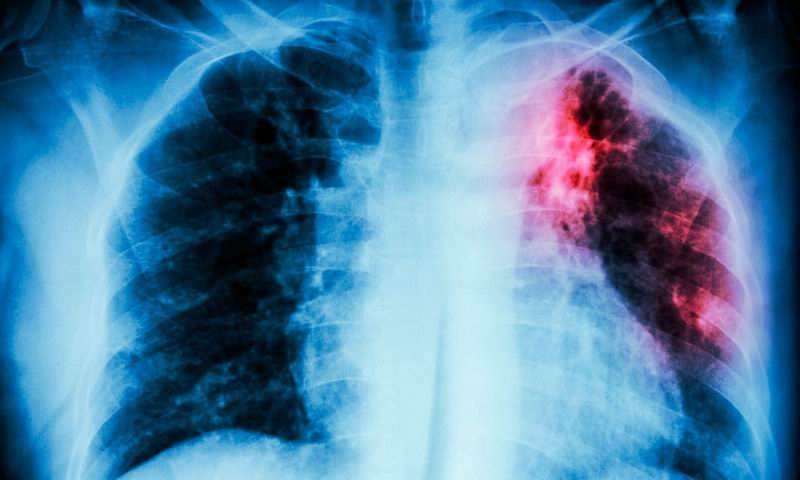

El especialista advirtió que se trata de una enfermedad de difícil diagnóstico porque «es como una gran simuladora, porque puede tener muchísimos síntomas, depende del órgano que tenga afectado». En ese sentido, explicó ante la emisora que se estima en que más del 80 por ciento de los casos de tuberculosis, la bacteria se asienta en los pulmones, generando determinados síntomas. Entre estos enumeró: malestar, pérdida de peso, tos intensa durante más de tres semanas, dolor de pecho, tos con catarro y hasta con sangre, debilidad muscular, fatiga, fiebre, falta de apetito, sudoración.